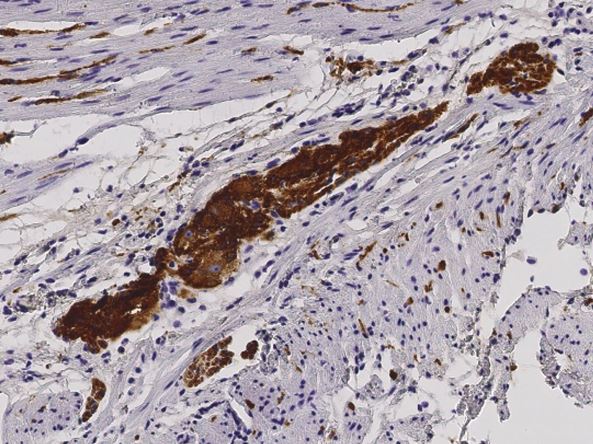

IHC-P analysis of human appendix tissue section using GTX02026 L1CAM antibody [014].

Dilution : 1:200